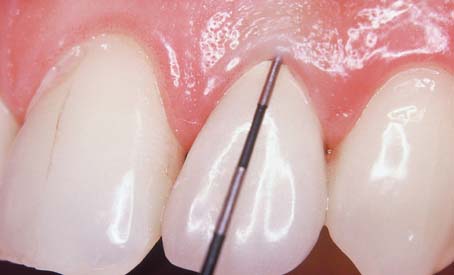

One advantage of partial-coverage restorations is that pulp health can be monitored with an electric pulp tester (Fig. 32-16), although the vitality of any tooth with a complete crown can still be assessed by thermal means. Correlating the histologic condition of a pulp directly with the patient’s response to pulp testing is difficult.33 Therefore, such results should be combined with other clinical data that result from careful patient history documentation and examination. Seeking the opinion of an endodontist is often advisable (Fig. 32-17). Radiographs provide useful information about the presence of periapical pathosis. Teeth with fixed restorations should be reviewed radiographically every few years. The use of a standardized technique enables the dentist to make an objective comparison with previous films. Although some studies have shown a high incidence of periapical disease associated with fixed prostheses,34,35 other studies have shown a low incidence of this complication.29,36,37